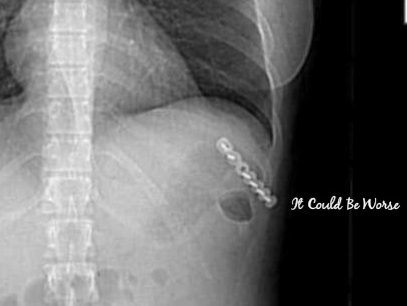

The positive is that I finally got imaging of the rib plate that had been placed in May for my Slipping Rib Syndrome at ribs 9-10. I was excited just to see what it looked like, to find out the details that I hadn’t been able to get with my online medical file – I hadn’t had imaging since before the procedure.

But, my ribs have also been an issue, with the neurectomy and rib plating procedures. Those are still healing, too, at 11 and 6 months later.

I do hate to admit I think there is another fracture, I have felt movement at the rib location directly above the plate. I am hoping that this is just a temporary sensation and not another fracture that will lead to popping and bone grinding, leaving me with another possible surgery if that is the case.

I think there is another fracture above the rib plate that was put in in May. I think the integrity of that costal cartilage has weakened and has created another dislocation, near my xiphoid process. And, I think that my first floating rib is moving, or slipping, up under the bottom portion of the rib plate.

Dr. London said that it was possible, that we would do a few imaging scans, like a CT scan and an ultrasound on my ribs near the rib plate. We discussed removing the rib tip of the slipping rib and the possibility of another rib plating. We discussed cryotherapy surgery to freeze-kill the nerves that were cut during the neurectomy surgery in January. This would stop the residual nerve pains and neuralgia that hits me right at the centerline-deadzone of my numb area.